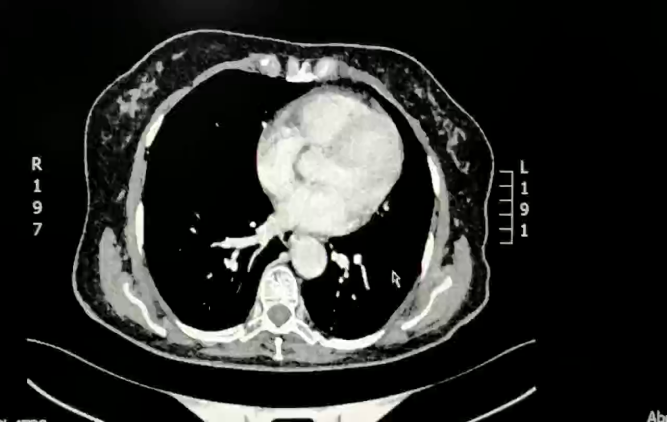

2022-05 复查CT

乙状结肠癌术后改变,同前相仿;左侧盆腔腰大肌旁混杂密度结节,多系术后改变,同前相仿。

肝尾状叶边缘、胰腺上方钙化结节,同前相仿;腹盆腔少量积液,腹膜转移,盆腔积液减少,余较前略较前变化不大。